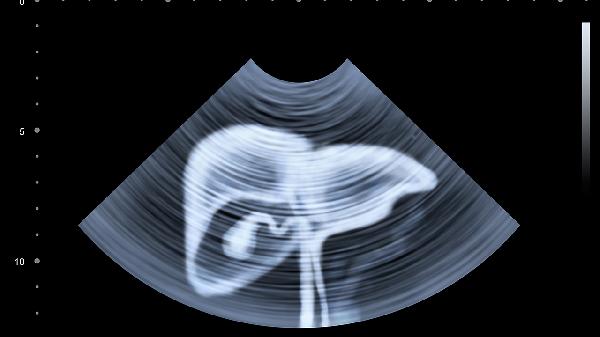

进食后胃部充满食物,超声波穿过胃肠气体时会发生散射,导致肝脏、胰腺等器官显像模糊。胆囊在消化期间会收缩排空胆汁,此时无法评估胆囊壁厚度或结石情况。高脂饮食还可能诱发胆囊剧烈收缩,造成假性胆囊炎影像。肠道蠕动加快也会干扰对阑尾、肠系膜淋巴结的观察。

部分特殊情况下允许进食后检查。孕晚期胎儿超声不受母亲饮食影响,膀胱超声需要适当憋尿反而建议饮水。急诊怀疑肠梗阻或阑尾炎时,即使进食也需立即检查。儿童或糖尿病患者可遵医嘱少量进食流质食物防止低血糖。